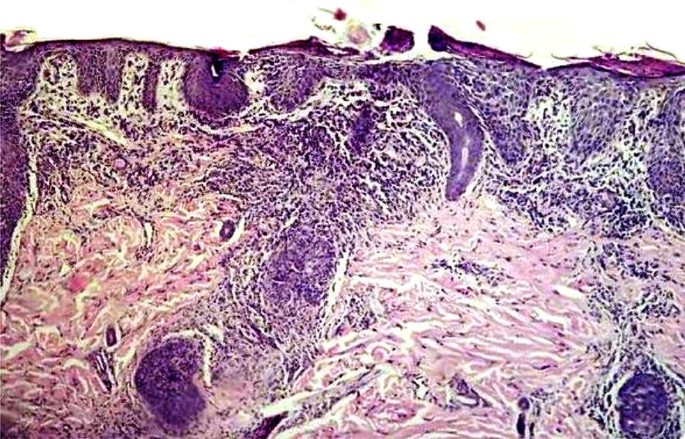

The participant in our study included a 3-year-old Caucasian girl born out of a first-degree consanguineous marriage, with a history of diarrhea (without blood and microbiologic tests failed to show specific pathogens onset at age 3 months), FTT (weight drop down two major percentile lines at age 6 months) and oral thrush (at age 4 months, resolved with 1% clotrimazole solution). The child had respiratory distress (chest X-ray reported with nonspecific air bronchograms), wheezing, erythroderma (diffused involving 50% of the body’s surface with exfoliation and responded moderately to immunosuppressive drug), alopecia and skin dryness. There was no family history of SCID and she had an unaffected male sibling. She did not suffer from lymphadenopathy, hepatosplenomegaly, pneumonia, invasive infection, liver involvement, BCGosis and eosinophilia. The pathological examination of the skin biopsy at the age of 18 months revealed acute as well as chronic inflammation extending from the upper to the deep dermis (Fig. 2).

Differentiation between GVHD and OS is often difficult in combined immunodeficiency with hypomorphic mutations only based on clinical and immunological phenotype [1]. Typical OS features can also be seen in some cases of maternally induced GVHD. Thus, some patients reported to have ‘Omenn’s syndrome’ may actually have had maternally-induced GVHD [13, 14]. In the current survey, the immunological and skin biopsies results of the patient were consistent with both GVHD and OS diseases. However, before confirmation of the maternal engraftment, the patient was evaluated based on the assumption that she was suffering from OS. The presence of maternal cells in the patient’s blood helped narrow the differential diagnosis in favor of microchimerism or GVHD.